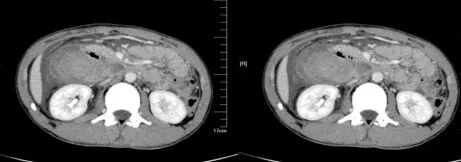

肾挫伤

肾挫伤是一种比较多见的肾损伤,肾组织损伤较轻,肾包膜和肾盂大多保持完整,肾实质内产生瘀血或血肿,并有少量血液流入肾盂导致血尿。肾挫伤在X线造影片上可不显示形态上的改变。一般均能自行愈合而不造成严重后果。